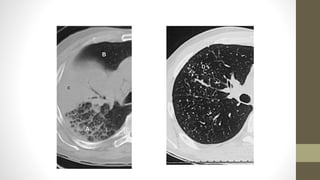

La Figura muestrauna enfermedad pulmonar intersticial difusa. La trama intersticial está aumentada, mientras que los alvéolos están aireados. Es crónica porque la trama pulmonar está distorsionada y nítida.

• En lafigura la TC muestra el intersticio distorsionado y bien definido y el pulmón aireado.

• Otra formade fibrosis es el «panal de abeja». La fibrosis forma múltiples quistes pequeños, a menudo apilados, justo subyacentes a la pleura. • Las Figuras muestran una radiografía y una TC con panalización.